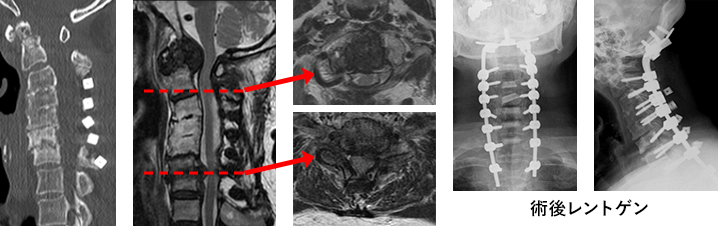

3. 頚椎手術(頚椎前方固定術、頚椎椎弓形成術、頚椎インストルメント手術)

頚椎手術は前方からあるいは後方から進入する方法に大きく2つに分かれます。頚椎前方固定術は頚椎を前から進入し、椎間板を郭清し、椎体を削って神経の圧迫を取り除き、金属製の内固定材(ケージ)と金属製のプレートで固定する手術です。必要に応じ骨盤や下腿から骨を採取します。また、骨を採取したあとの骨盤にはセラミックなどの人工物を補填する場合もあります。頚椎椎弓形成術は後方から脊柱管を広げ、脊髄の圧迫をとる手術です。手術の選択は患者さんの状態によって決定します。

④ 頚椎後方インストルメント手術

後方から金属(インストルメント)を用いて固定します。多くは椎弓形成を追加します。

下の画像は透析脊髄症に対する再手術例です。インストルメントで頚椎を再建しています。